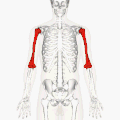

![]() Position of humerus (shown in red) from an anterior viewpoint | |

The humerus (/ˈhjuːmərəs/; pl.: humeri) is a long bone in the arm that runs from the shoulder to the elbow. It connects the scapula and the two bones of the lower arm, the radius and ulna, and consists of three sections. The humeral upper extremity consists of a rounded head, a narrow neck, and two short processes (tubercles, sometimes called tuberosities). The shaft is cylindrical in its upper portion, and more prismatic below. The lower extremity consists of 2 epicondyles, 2 processes (trochlea and capitulum), and 3 fossae (radial fossa, coronoid fossa, and olecranon fossa). As well as its true anatomical neck, the constriction below the greater and lesser tubercles of the humerus is referred to as its surgical neck due to its tendency to fracture, thus often becoming the focus of surgeons.